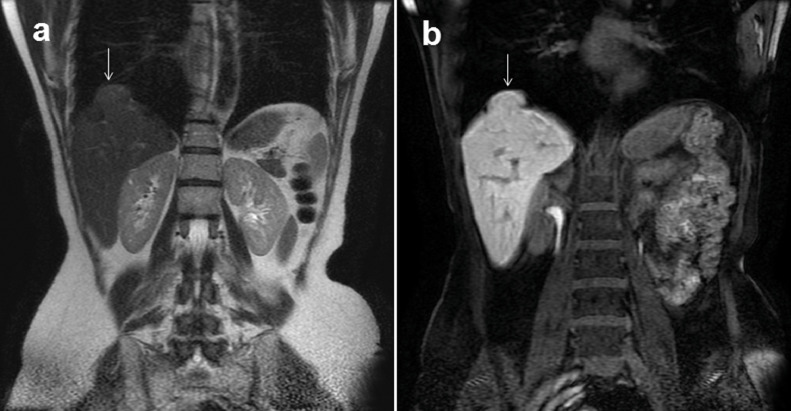

Fig.3 – MR.

Coronal T2-weighted acquisition and spoiled GRE 3D-T1 weighted after intravenous administration of hepatospecific contrast agent-MR (Gd-EOB-DTPA, Primovist) (b) show herniation of hepatic tissue into thoracic cavity through a diaphragm defect. In T2-weighted acquisition (a) herniated tissue shows isointense signal with some weakly hyperintense areas referable to compressed liver parenchyma; in images after contrast agent-MR (b) it is possible to appreciate regular uptake of contrast agent and homogeneous signal with respect to underlying liver parenchyma which confirms hepatic origin of herniated tissue.